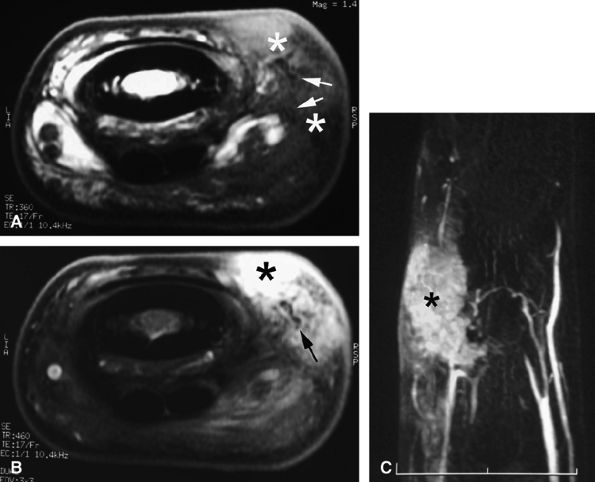

seen with synovial sarcomas. Bone and joint invasion is possible.168 Ultrasonography shows a nonspecific solid mass with a variable color Doppler signal. MR images are specific, depicting a well-defined mass with hemosiderin deposits. Typical signal void artifacts are seen on all sequences, particularly on gradient-echo images, and a more heterogeneous and predominantly low signal is found on T2-weighted images.162,166,169 The lesion typically enhances after intravenous injection of gadolinium (Fig. 11.74). The tendon sheath of the flexor digitorum tendons is usually partially or totally enveloped; the extensor tendons are less commonly involved. Some lesions may be more aggressive, and diffuse lesions are seen in multiple locations with invasion of both the flexor and extensor tendons (Fig. 11.75).170

FIGURE 11.74 ● Giant cell tumor of the tendon sheath. Sagittal T2-weighted image (A) and post-contrast T1-weighted image (B) show a palmar mass (arrows) close to the sheath of the flexor tendons with predominant low signal (arrowhead) on the T2-weighted image and strong enhancement following contrast administration.

FIGURE 11.75 ● Aggressive giant cell tumor of the tendon sheath. Sagittal post-contrast 3D gradient-echo (A) and axial T1-weighted (B) images depicting a multinodular tumor invading the flexor and extensor tendons as well as the head of the phalanx (arrow).